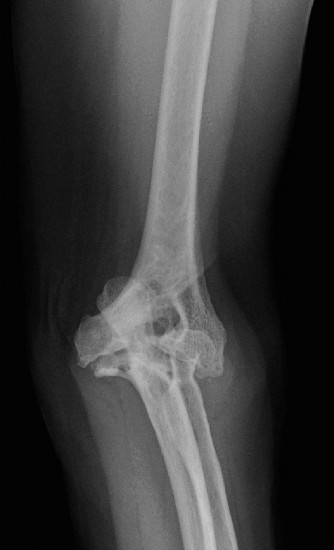

Definitive treatment and long-term expectations? CASE 35 A 54-year-old male presented to the ED with left elbow pain after sustaining an injury in a low speed motor vehicle accident. He denied any other injuries. On examination, he had no open injuries and was neurovascularly intact. He had gross deformity about the elbow. His images are below (Figs. 2–89 to 2–92).

Figure 2–89 Pre- and post-reduction films showing complex elbow dislocation, coronoid fracture.

Figure 2–90 Pre- and post-reduction films showing complex elbow dislocation, coronoid fracture.

Figure 2–91 Pre- and post-reduction films showing complex elbow dislocation, coronoid fracture.

Figure 2–92 Pre- and post-reduction films showing complex elbow dislocation, coronoid fracture.

What is the diagnosis?

- Posterolateral simple elbow dislocation

- Posterolateral complex elbow dislocation

- Posteromedial complex elbow dislocation

- Posteromedial simple elbow dislocation

Discussion

The correct answer is (C). Posteromedial complex elbow dislocation. This injury is proposed to result from axial load combined with posteromedial rotation, varus force, and elbow flexion. This is opposed to the more frequently seen posterolateral dislocation. There is a fracture of the coronoid, which is typical for this type of injury.